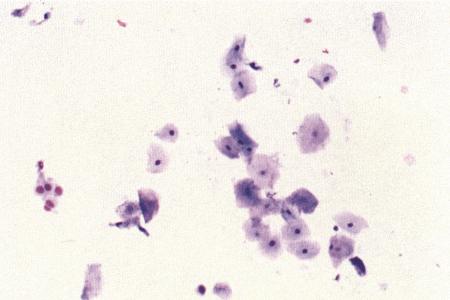

Фиг. 2.2.

Вагинальные выделения кошки (а). Выделения, типичные для фазы эструса. Большая часть клеток представляет собой безъядерные кератинизированные клетки или клетки с пикнотическим ядром. Присутствуют промежуточные клетки (b). Выделения, характерные для метэструса, — «течки», иногда наблюдаемой у кошек в конце эструса. Присутствуют поверхностные и промежуточные клетки, повышено содержание лейкоцитов. Этот короткий метэструс наблюдается в течение 24–48 часов (см. Приложение)